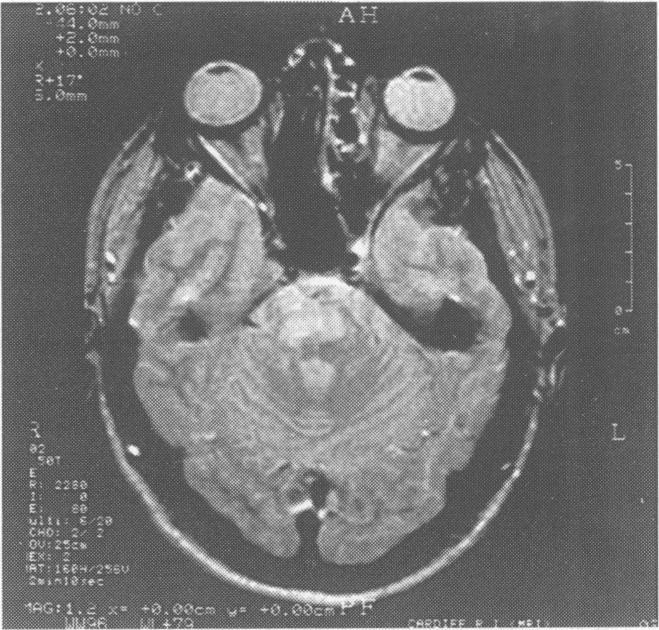

Mills' syndrome: ascending (or descending) progressive hemiplegia: a hemiplegic form of primary lateral sclerosis?

J Neurol Neurosurg Psychiatry. 1994 Oct;57(10):1280-1. doi: 10.1136/jnnp.57.10.1280.